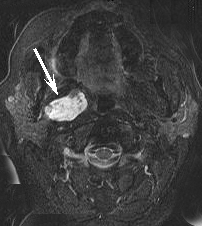

SCAN

CT Scan and MR Scan from the same patient on the same day. On the left, metal scatter artifact from metallic fillings in the teeth almost completely obscure a tumor that is easily seen by MRI using metal suppressing techniques on the right.